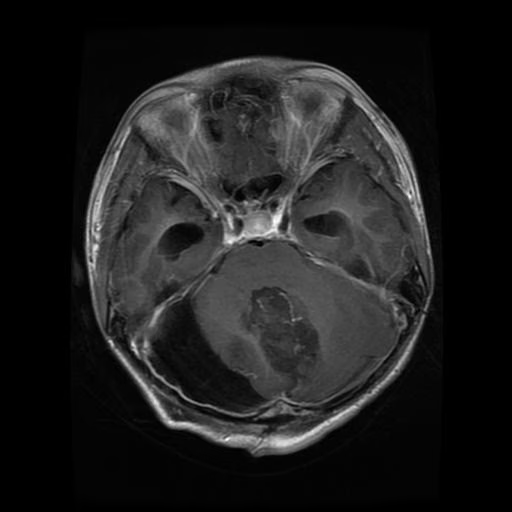

2. BRISC 2025 脑肿瘤 MRI 分割与分类数据集

BRISC 2025 是一个用于脑肿瘤分割与分类的磁共振成像(MRI)数据集,该数据集同时支持两类任务:一是分类任务,即基于 MRI 图像的多类肿瘤识别;二是分割任务,即利用配对的 MRI 图像与掩模进行像素级肿瘤区域检测。其组织结构清晰,图像与掩模文件名严格对齐,便于直接应用于深度学习模型的训练与验证。

数据集示例